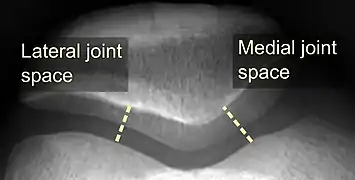

- The patellofemoral index is the ratio between the thickness of the medial joint space and the lateral joint space (L). With the knee 20° flexed, it should measure 1.6 or less.[16]